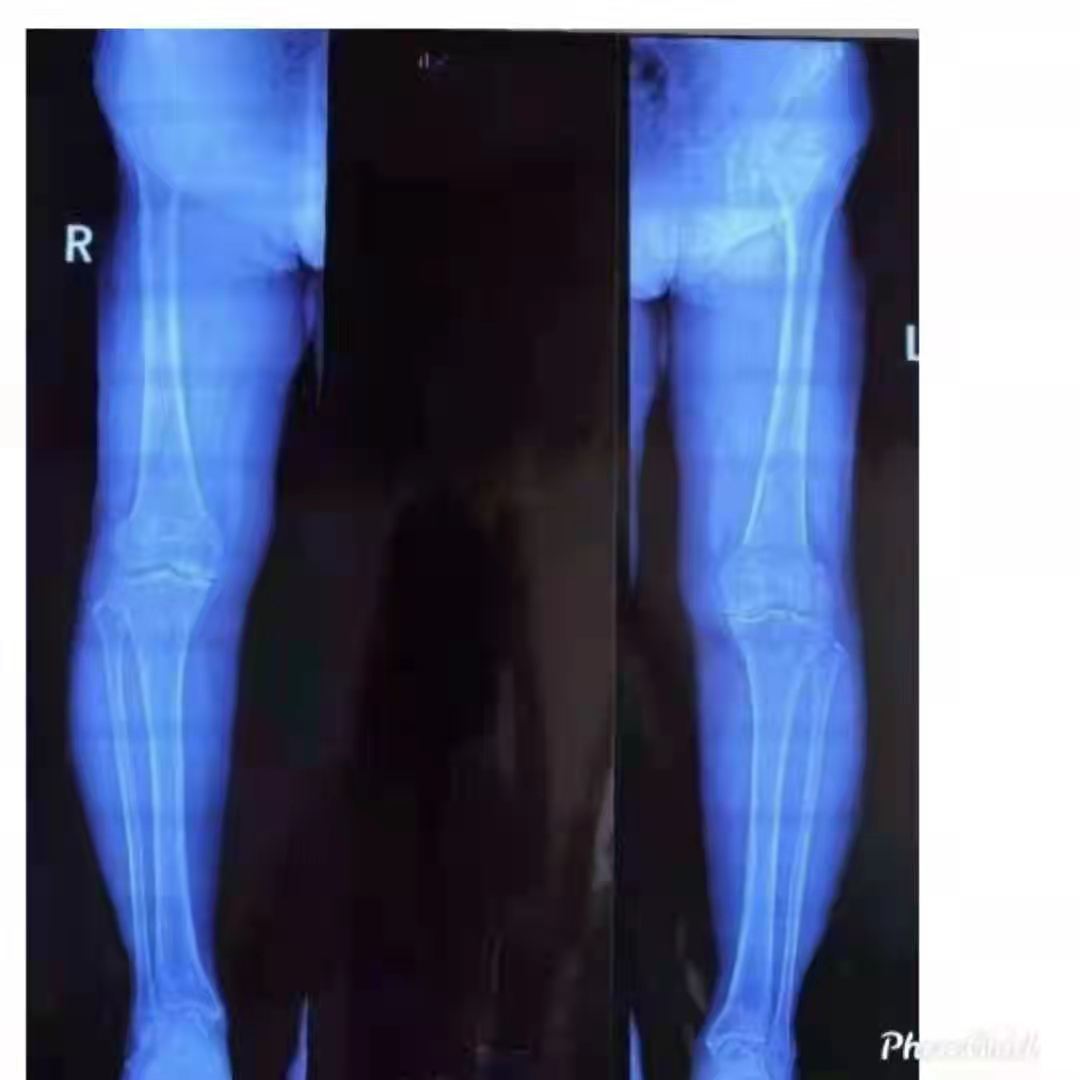

幸運(yùn)的是,王女士慕名來到了山亭誠德骨科醫(yī)院,專家檢查診斷,發(fā)現(xiàn)王女士雙側(cè)膝關(guān)節(jié)內(nèi)側(cè)磨損嚴(yán)重,外側(cè)部分和前后交叉韌帶上好,因此采取雙側(cè)同期部分置換。應(yīng)用牛津單髁活動(dòng)平臺,手術(shù)屬于保膝范疇,保留了好的部分,修補(bǔ)了磨損重的部分,病人感受好,恢復(fù)快,功能好。如果錯(cuò)過這個(gè)修補(bǔ)的時(shí)機(jī),整個(gè)關(guān)節(jié)都磨損了,只能進(jìn)行全膝置換了。